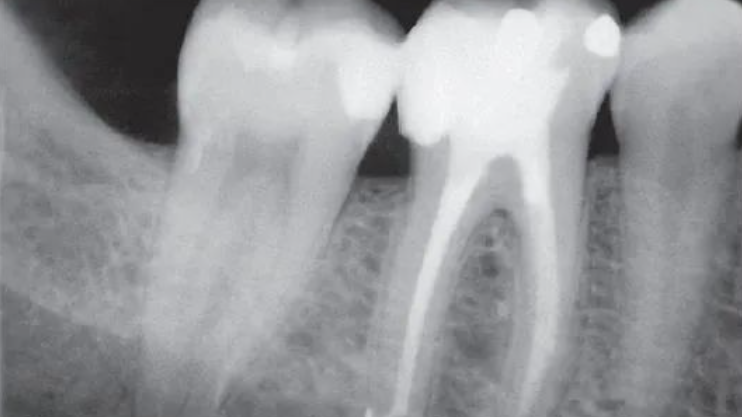

王某,女,48岁,下颌左侧第二前磨牙因急性牙髓炎来院开髓,封入失活剂后,8天后感觉疼痛才复诊去出失活剂,发现已引起砷性根尖炎。经此法治疗,无叩痛根充,经追踪观察,良好。